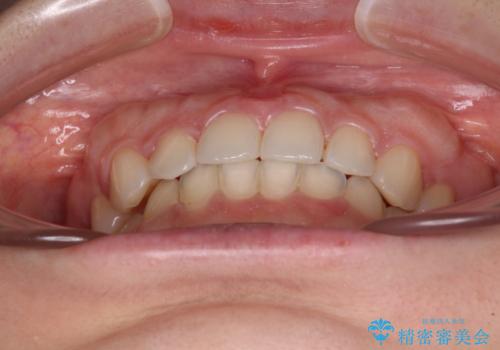

ギリギリとなりましたが、結婚式直前にワイヤー装置を外すことができました。

ワイヤー装置除去後に細かい部分を短期間のマウスピース矯正にて仕上げました。